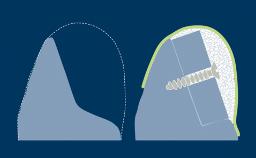

- describe the surgical steps and considerations that precede simultaneous augmentation

- describe the treatment concept and surgical steps for simultaneous contour augmentation